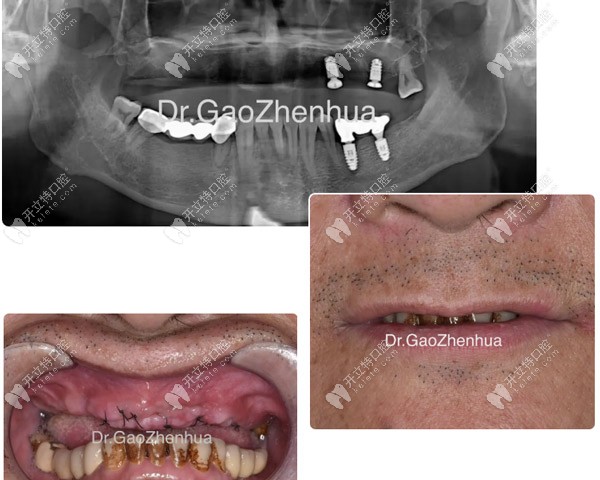

馮先生決定來鼎植治療缺骨問題,是因為一年前做的6顆即刻負重短植體全部松動脫落,在廣州各大口腔尋醫(yī)無效后才去的治療。

馮先生種植失敗后拍的CT片

馮先生種植失敗后拍的CT片▲

結(jié)果顯示:牙槽嵴多處缺骨、牙齒骨質(zhì)疏松,后牙區(qū)多位點缺骨并與竇腔貫連,好在結(jié)節(jié)翼板區(qū)骨量尚可

顴種植位點不得已還是放在貫通位點,竇底適當植骨,前牙區(qū)靠鼻底硬骨板雙皮質(zhì)固位獲得穩(wěn)定性,經(jīng)過2個小時的手術(shù),實現(xiàn)了即刻負重的預(yù)期!